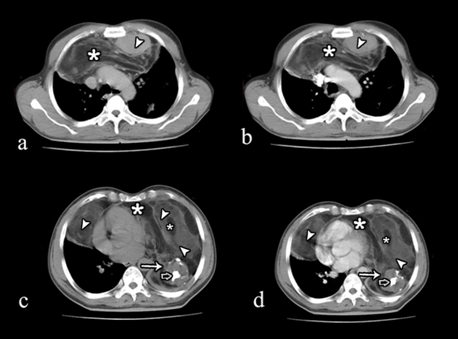

The MRI scan confirmed the same findings and clearly depicted the fatty, soft tissue and cystic components (Figure 3). Encasement of the vessels was seen. There was pericardial invasion on left side.

Figure 3: (a) Axial MRI T1W scan, (b) T2W scan, (c) Fat suppressed T2W and (d) BTFE images at the level of ventricles showing heterogeneous mass with solid component (arrow head), fat (*), cystic area (solid arrow) and nodular calcification (open arrow), occupying anterior half of right hemithorax and complete left hemithorax with pericardial invasion.